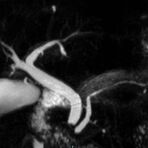

MRCP

• Gallenwegssystem

• Nichtinvasive Darstellung der Gallenwege (MRCP)

• Abklärung der Ursache einer Gallenabflussbehinderung (Tumor, Gallensteine, Entzündung)

MR-Angiografie (MRA)

Angiographie ohne Kontrastmittel

• MR-Angiografie ohne Kontrastmittel

• Time of Flight (TOF)-Angiographie

• Phasenkontrastangiographie (PCA). Geeignet zur Quantifizierung Stenose-/Insuffizienzgrad z.B. bei Herzklappen, falls echokardiographisch die Untersuchungsbedingungen eingeschränkt sind.

Je nach Fragestellung und Körperregion Gefäßdarstellung ohne Kontrastmittel bei Kontrastmittelunverträglichkeit oder terminaler Niereninsuffizienz möglich.

Ganzkörper Angiographie mit Kontrastmittel

• MR-Angiographie mit Kontrastmittel

• Erfassung arterieller und venöser Gefäße/Bypässe aller Körperregionen mit 3D-Rekonstruktion

• je nach klinischer Fragestellung zeitaufgelöste MR-Angiographie (4D-MRA) z.B. bei Frage arteriovenöse Fistel/ Shunt oder Darstellung Unterschenkelarterien vor geplanter Bypassoperation.